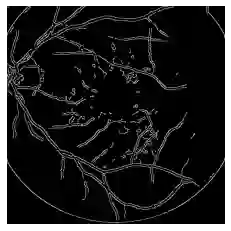

Domain Adaptation is a technique to address the lack of massive amounts of labeled data in unseen environments. Unsupervised domain adaptation is proposed to adapt a model to new modalities using solely labeled source data and unlabeled target domain data. Though many image-spaces domain adaptation methods have been proposed to capture pixel-level domain-shift, such techniques may fail to maintain high-level semantic information for the segmentation task. For the case of biomedical images, fine details such as blood vessels can be lost during the image transformation operations between domains. In this work, we propose a model that adapts between domains using cycle-consistent loss while maintaining edge details of the original images by enforcing an edge-based loss during the adaptation process. We demonstrate the effectiveness of our algorithm by comparing it to other approaches on two eye fundus vessels segmentation datasets. We achieve 1.1 to 9.2 increment in DICE score compared to the SOTA and ~5.2 increments compared to a vanilla CycleGAN implementation.